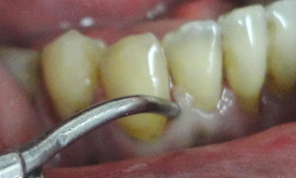

Esta paciente veio ao consultório com a indicação de uma raspagem nesta região. Pois segundo seu Dentista, sua gengiva esta inflamada. Um exame radiográfico foi realizado, mostrando uma grande perda de osso, os dentes apresentavam uma grande mobilidade, com um prognóstico muito sóbrio. O caso da paciente, foi minuciosamente discutida com a paciente, mostrado que os dentes da bateria inferior anterior estavam perdidos, não haveria meios mais, de serem recuperados. Foi um choque no início para a paciente, contudo após um exame geral em sua boca, mostrando as profundas bolsas intraósseas, com inflamações generalizadas, e o risco que ela corria, não somente pela perda dos dentes, mas comprometimentos gerais incluindo problemas sérios cardíacos, ela se conscientizou da necessidade urgente de tratamento.

No início da profilaxia pré-cirúrgica, com as pontas de ultrassom, podemos demonstrar a paciente a necessidade do procedimento indicado. Os dentes praticamente seriam removidos apenas com uma profilaxia rigorosa. Em certos casos, e dependendo dos pacientes, é importante mostrar as alterações patológicas, assim como documentar os procedimentos, que forem realizados. Os dentes foram extraídos, pois, estavam condenados. Apaciente não usava, pois estavam moles e doíam.